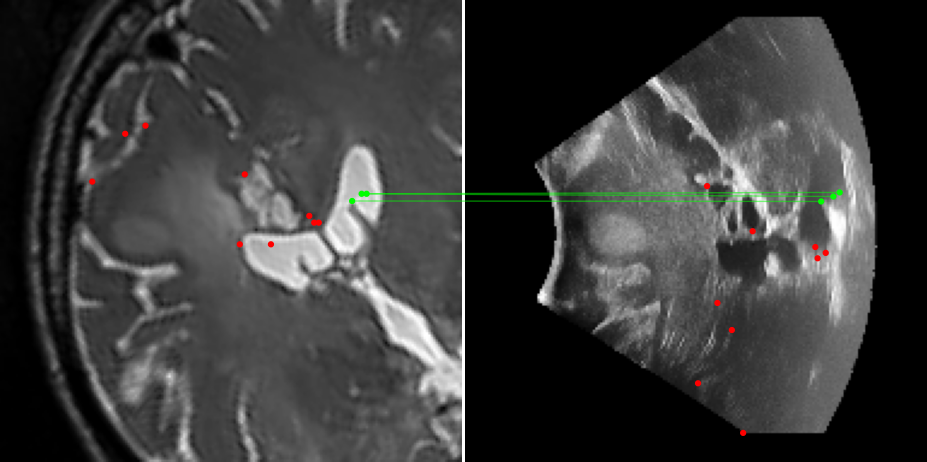

Figure 3: Examples of matching on three cases, one per column (MR on left and US on right). From top to bottom: SIFT+Cosine, MIND+Cosine, SP+Cosine, SP+LG, Ours+LG, Ours+Cosine. Correct matches recovered by each method are shown in green lines and mismatched are shown with a red dot.

To evaluate the performance of our model against existing image methods, we compared it to three approaches: SIFT [16], which remains the standard for keypoints matching, SuperPoint (SP) [3] built using a self-supervised learning approach and MIND [10], a modality-invariant descriptor for medical imaging, that although not designed for 1-to-1 keypoint matching, is extensively used for multimodal medical image registration through grid regularizing. We use SIFT and SP as keypoints detectors and descriptors, while we combine MIND with SP keypoints since it only provides a descriptor. We match these descriptors using both Cosine similarity and the deep neural network LightGlue (LG) [15] when possible (SP and Ours). Results reported in Table 2 and shown in Fig. 3 show that our approach outperforms these methods in terms of matching score, precision, and number of matched points. We only report results on three cases for readability reasons. Associating our descriptor with Cosine and LG reached similar performance depending on the metric.